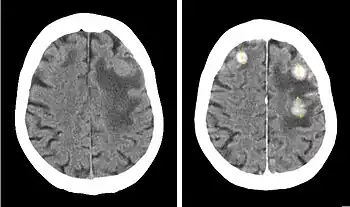

Iopentol (trade name Imagopaque) is a pharmaceutical drug that was used as a radiocontrast agent for X-ray imaging in Europe.[1]

Uses included arteriography (imaging of arteries), venography (imaging of the veins) and CT scan enhancement, urography (imaging of the urinary system), arthrography (imaging of the joints), endoscopic retrograde cholangiopancreatography (ERCP; imaging of bile and pancreatic duct), hysterosalpingography (imaging of the uterus and fallopian tubes), and gastrointestinal studies.[1]

Iopentol is an iodine-containing, water-soluble radiocontrast agent. The iodine atoms readily absorb X-rays, resulting in a higher contrast of X-ray images. It has a low osmolality, meaning that the solution has a relatively low concentration of molecules; this is usually associated with fewer adverse effects than high-osmolality contrast agents.[1][2]